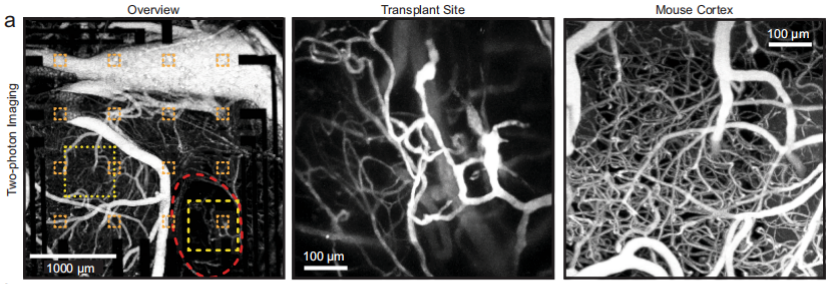

研究人员运用体内双光子成像和免疫染色技术,对类器官移植物与周围宿主组织的整合情况进行了观察。

血管化一直是类器官构建中的难点问题,在类器官植入的9到10周后,对小鼠注射血管内示踪剂Alexa Fluor 680葡聚糖。通过双光子显微镜,发现类器官植入区域都含有小鼠脉管系统。而且与周围皮质相比,类器官区域的血管密度较低。

类器官血管化的体内成像

图片来源:Nat Commun 13, 7945 (2022)